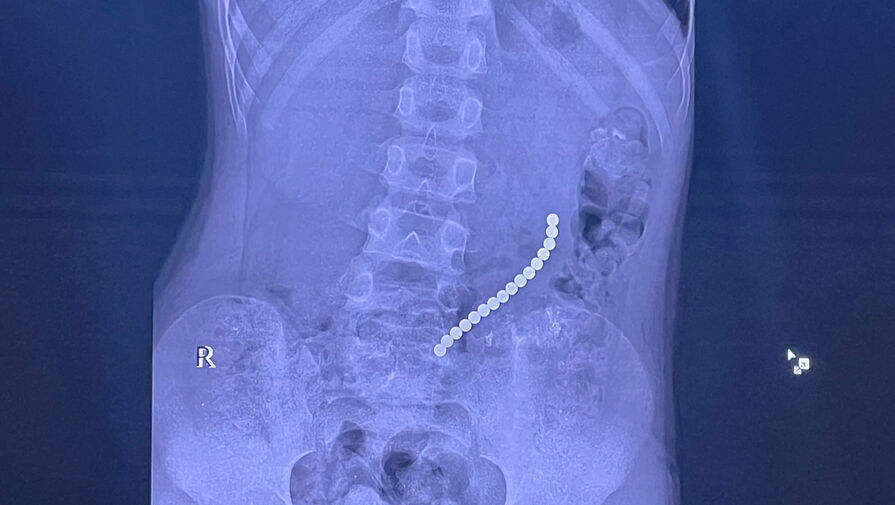

Российский школьник проглотил 16 магнитных шариков

В Иркутске спасли восьмилетнего мальчика с 16 магнитами в желудке и кишечнике

Врачи Иркутской областной детской клинической больницы спасли восьмилетнего пациента, который проглотил магниты. Об этом сообщил главврач больницы, член-корреспондент РАН Юрий Козлов на своей странице во «ВКонтакте».

Медик отметил, что ребенок поступил в медучреждение с жалобами на «острый живот». На обследовании специалисты обнаружили 16 магнитов, которые соединились между собой в различных сегментах внутренних органов.

«Очень редкое сочетание: одни магниты находились в желудке, другие — в начальном отделе тонкой кишки. Это привело к образованию фистулы — сообщению между желудком и кишкой», — поделился Козлов.

С помощью технологий минимально-инвазивной хирургии врачи извлекли инородные предметы, разделили органы и восстановили их целостность.